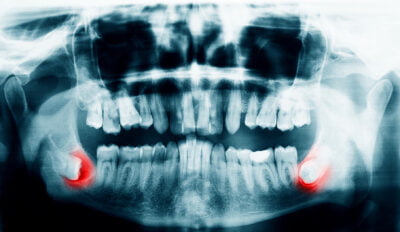

- The teeth are erupting crooked or are impacted (erupting sideways). This situation is potentially harmful to adjacent bone and/or teeth

Wisdom teeth – also known as the third molars – are the last teeth to erupt, typically appearing between the ages of 17 and 25. Unfortunately, these teeth often present problems. Because of this, your dentist may recommend extraction (removal). Wisdom tooth extraction is currently performed on over five million patients in the U.S. alone, and is a typical procedure here at the Yuba City Dentistry Group.